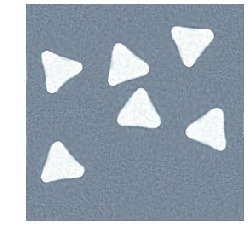

5.4 Inconsistent topology and intensities

Here, both topology and intensities of the template differ from those in the target. The template, which is shown in fig. 3(a), is registered against tomographic data shown in fig. 3(c). The (unknown) target used for generating the data is shown in fig. 3(b). Also, data has a noise level corresponding to a \acPSNR of and kernel size is , which should be compared to the size of the image domain . The final reconstruction is shown in fig. 3(h), which is to be compared against the target in fig. 3(b). Figure 3 also shows image, deformation and template trajectories.

We clearly see that metamorphosis based indirect registration can handle a template where both intensities and the topology are wrong. In particular, we can see follow both the deformation of the template and the appearance of the white disc.